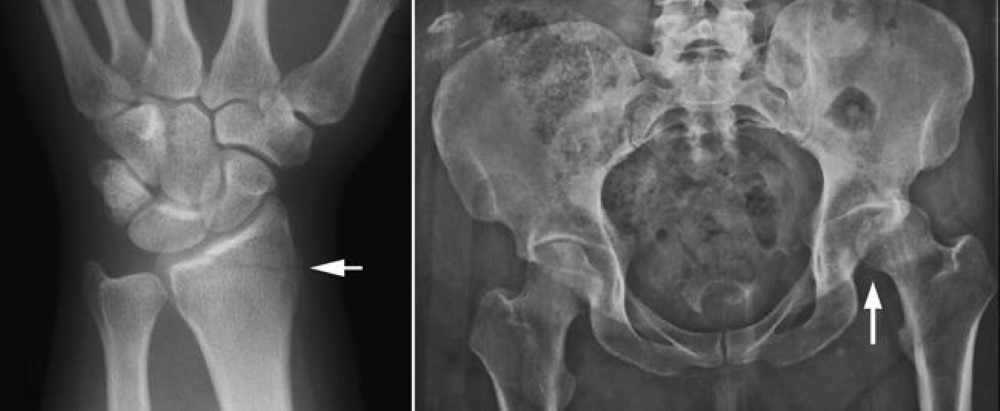

Οι ακτινογραφίες είναι η πιο κοινή και ευρέως διαθέσιμη διαγνωστική τεχνική απεικόνισης. Μπορούν να παρέχουν στον γιατρό σας σημαντικές και δυνητικά σωτήριες πληροφορίες για πολλές ιατρικές καταστάσεις και χρησιμοποιούνται συχνά για την ανίχνευση καταγμάτων οστών και εξαρθρώσεων μετά από πτώσεις και ατυχήματα.

Μελέτες δείχνουν ότι η έκθεση ενός αγέννητου μωρού σε περισσότερα από 10 rad αυξάνει τον κίνδυνο γενετικών ανωμαλιών, μαθησιακών δυσκολιών, οφθαλμικών προβλημάτων και παιδικών καρκίνων. Ωστόσο, οι περισσότερες συνήθεις ακτινογραφίες μυοσκελετικού συστήματος – ιδιαίτερα εκείνες που δεν κατευθύνονται προς την κοιλιά ή τον κορμό – είναι πολύ πιο αδύναμες από αυτό και εκθέτουν το αναπτυσσόμενο μωρό μόνο σε ένα μικρό κλάσμα ραδιοσυχνοτήτων.

Για παράδειγμα, η κατά προσέγγιση ποσότητα ακτινοβολίας που λαμβάνει ένα αγέννητο μωρό από τις πιο συχνά διαγνωστικές ακτινογραφίες περιλαμβάνει:

- Λιγότερο από 1 millirad για ακτινογραφία των άνω ή κάτω άκρων

- Λιγότερο από 100 millirad για ακτινογραφία θώρακος

- 40-240 millirad για ακτινογραφία της λεκάνης

- 200-245 millirad για ακτινογραφία κοιλίας

- 51-370 millirad για ακτινογραφίες ισχίου και μηριαίου οστού (μηριαίος)